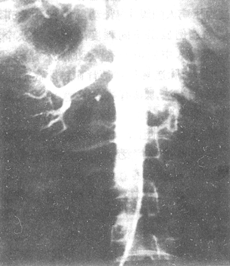

⑵瞭解腎動脈主幹形象以及有無分支或迷走血管:腎動脈有狹窄時,觀察狹窄部位、範圍、程度以及有無狹窄後擴張。病變性質可從影像形態分析(圖1、2、3、4):由於動脈粥樣硬化所致的,可為①腎動脈呈現斑塊樣的不規則;②狹窄和梗阻多呈錐形;③狹窄為偏心性的;④鈣化形成;⑤病變首發部位在腎動脈開口或近端段和⑥腹部有他血管可有粥樣硬化現象。纖維肌肉增生的改變:①長而光滑的狹窄;②長而不規則念珠狀的狹窄;③散在的網狀狹窄和④病變在腎動脈的中1/3和遠端1/3。多發性大動脈炎的改變:①腹主動脈管腔呈現粗細不勻或比較均勻,邊緣較光滑的向心性狹窄或阻塞;②少數為膨脹型包括動脈瘤形成,有的顯示膨脹與阻塞并存;③腎動脈在開口或近心段有局限性狹窄和阻塞,伴有狹窄後擴張和④大動脈炎為多發性病變,可累及腹、降主動脈及其多個分支。

圖1 腹主-腎動脈造影顯示右腎動脈閉塞,左腎動脈狹窄

圖2 腹主-腎動脈造影顯示節段狹窄型腹主動脈炎併發腎動脈狹窄

圖3 腹主-腎動脈造影顯示閉塞型腹主動脈炎併發腎動脈狹窄

圖4 腹主-腎動脈造影顯示膨脹型腹主動脈炎併發腎動脈狹窄